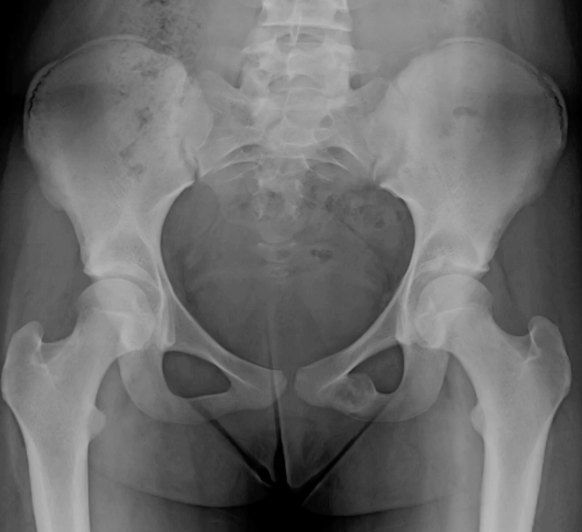

polyostotic Fibrous dysplasia